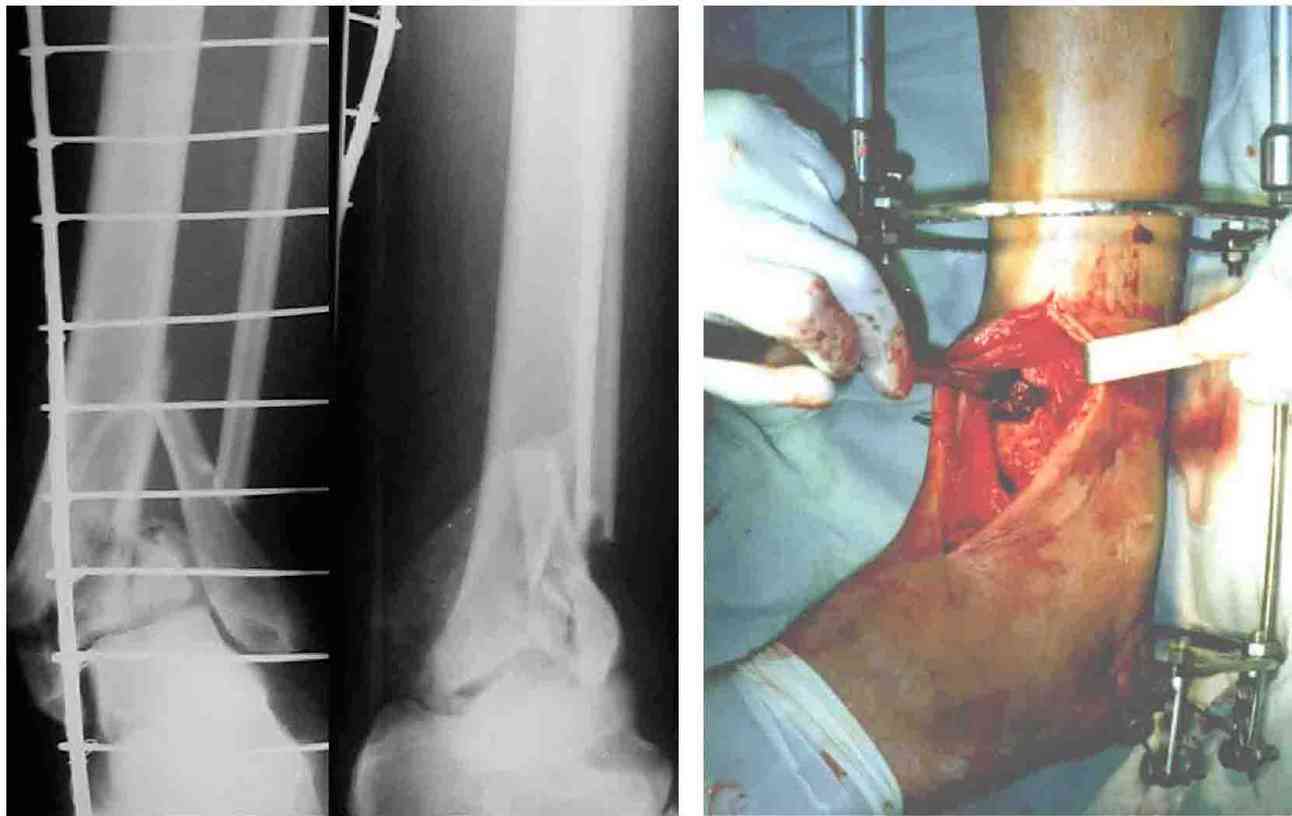

Во вложении - картинки из моей книжки как раз по этой теме

Схемы коррекции различных видов смещения в аппарате

Коррекция длины

Коррекция ротации

Коррекция ширины

В следующих письмах - дополнительные иллюстрации

Открытая репозиция.

Ничто особо не мешает, наоборот - все видно, требования к фиксации не очень высоки - можно просто фиксировать спицей или винтомю Внешний аппарат берет основную нагрузку

Пример -

задний край и диафиз

По поводу конкретного вопрошаемого случая:

1. Скорее всего в аппарате удасться вывести закрыто всё, кроме внутренней лодыжки. Открывайтесь и фиксируйте либо спицей с упором,

либо винтом.

2. ЭОП - очень спорное достижение в таких случаях. Сильные искажения.

Буквально вчера переделывали практически похожий случай. На ЭОПе всё идеально. На пленке - ступенька переднего края. Брали повторно, но уже

пригласили рентгенлаборантку в операционую сделать снимок.

3. Последнее время всё чаще делаем аппарат Илизарова в симбиозе с винтами, которыми фиксируем края (передний и задний), лодыжки и теперь - диафиз.

Позволяет пораньше снять аппарат.